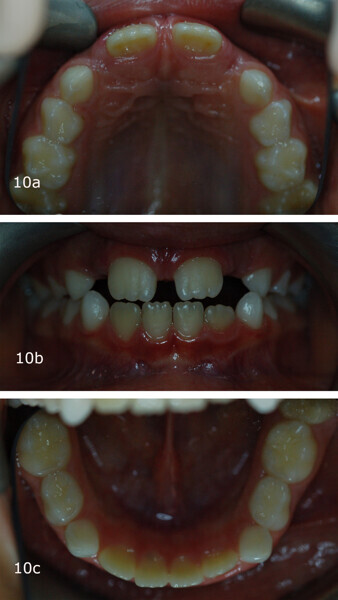

The 8-year-old male patient presented with a diastema between teeth #11 and 21 and non-eruption of teeth #12 and 22 (Fig. 1). The patient underwent a thorough orthodontic examination, including intra-oral photographs, extra-oral photographs, cephalometric radiography of the skull with cephalometric tracing, dental panoramic tomograms, impressions by intra-oral scanning, and functional and phonetic tests. Intra-oral examination (Fig. 2) and pattern analysis showed a Class I molar and canine relationship and contraction of the maxillary arch, displaced pre-contact between teeth #63 and 73, a 3.7 mm diastema between teeth #11 and 21, a mandibular midline deviation to the left, a maxillary midline to the right, and an open bite (−1.5 mm).

After 18 months of therapy, a case reassessment was carried out to verify that the goals had all been achieved (Fig. 8). Comparison of extra-oral photographs at the start of treatment (T0) and end of treatment (T1; Fig. 9) showed that excellent balance of the patient’s face had been achieved with a regular, symmetrical smile. Comparison of the intra-oral photographs (Fig. 10) and models (Fig. 11) also showed wider and more harmonious arch forms, closure of the anterior diastema, closure of the open bite and recentring of the mandibular midline. Excellent gingival trophism had also appeared.